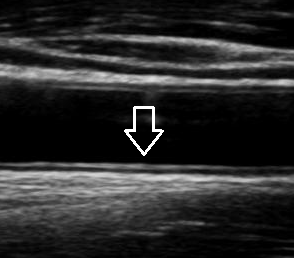

경동맥 초음파는 7MHz 이상의 선형 탐촉자를 사용해 경부 혈관의 내중막두께(IMT), 죽상경화반(플라크), 혈전, 박리, 협착 정도 등을 평가합니다.

경동맥 초음파는 목의 큰 동맥(총경동맥·내경동맥·외경동맥) 벽과 혈류를 실시간으로 확인하는 비침습적 검사입니다. 경동맥 초음파 검사로 알 수 있는 병은 대체로 심뇌혈관질환 위험이 의심되거나, 일과성허혈발작(TIA)·편마비 등 신경학적 증상이 있을 때, 또는 수술·시술 전후 평가에 표준적으로 활용됩니다. B-모드(흑백) 영상으로 혈관벽 두께와 플라크를 보고, 도플러로 혈류 속도와 방향을 정량화해 협착 정도를 평가합니다. 방사선 노출이 없고 10-20분 내외로 끝나며 반복 추적에 유리합니다.

- 과정: 검사대에 누운 뒤 젤을 바르고 양측 경동맥을 위·아래로 따라가며 B-모드와 도플러를 시행합니다. 필요 시 척추동맥 혈류 방향도 확인합니다. 통증·방사선 노출·조영제 사용이 없습니다.